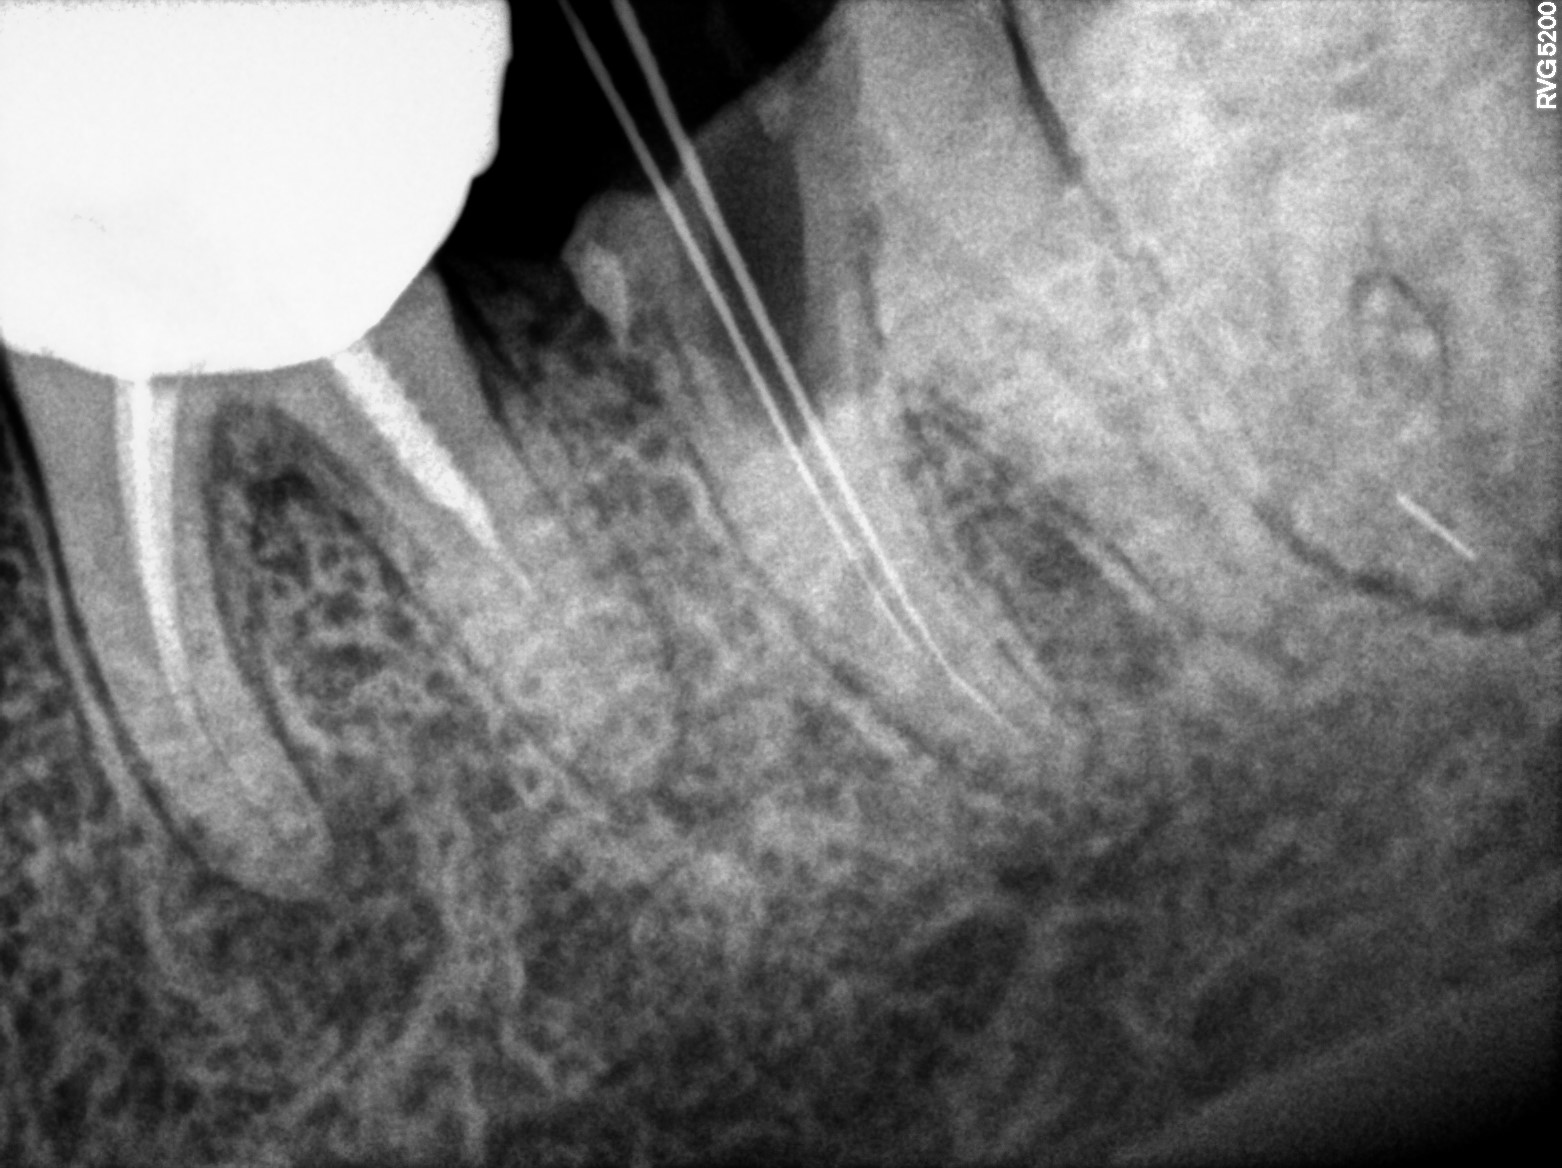

Dental Radiographs FHIR: DocumentReference · LOINC 24641-7

R38.jpg

24641-7